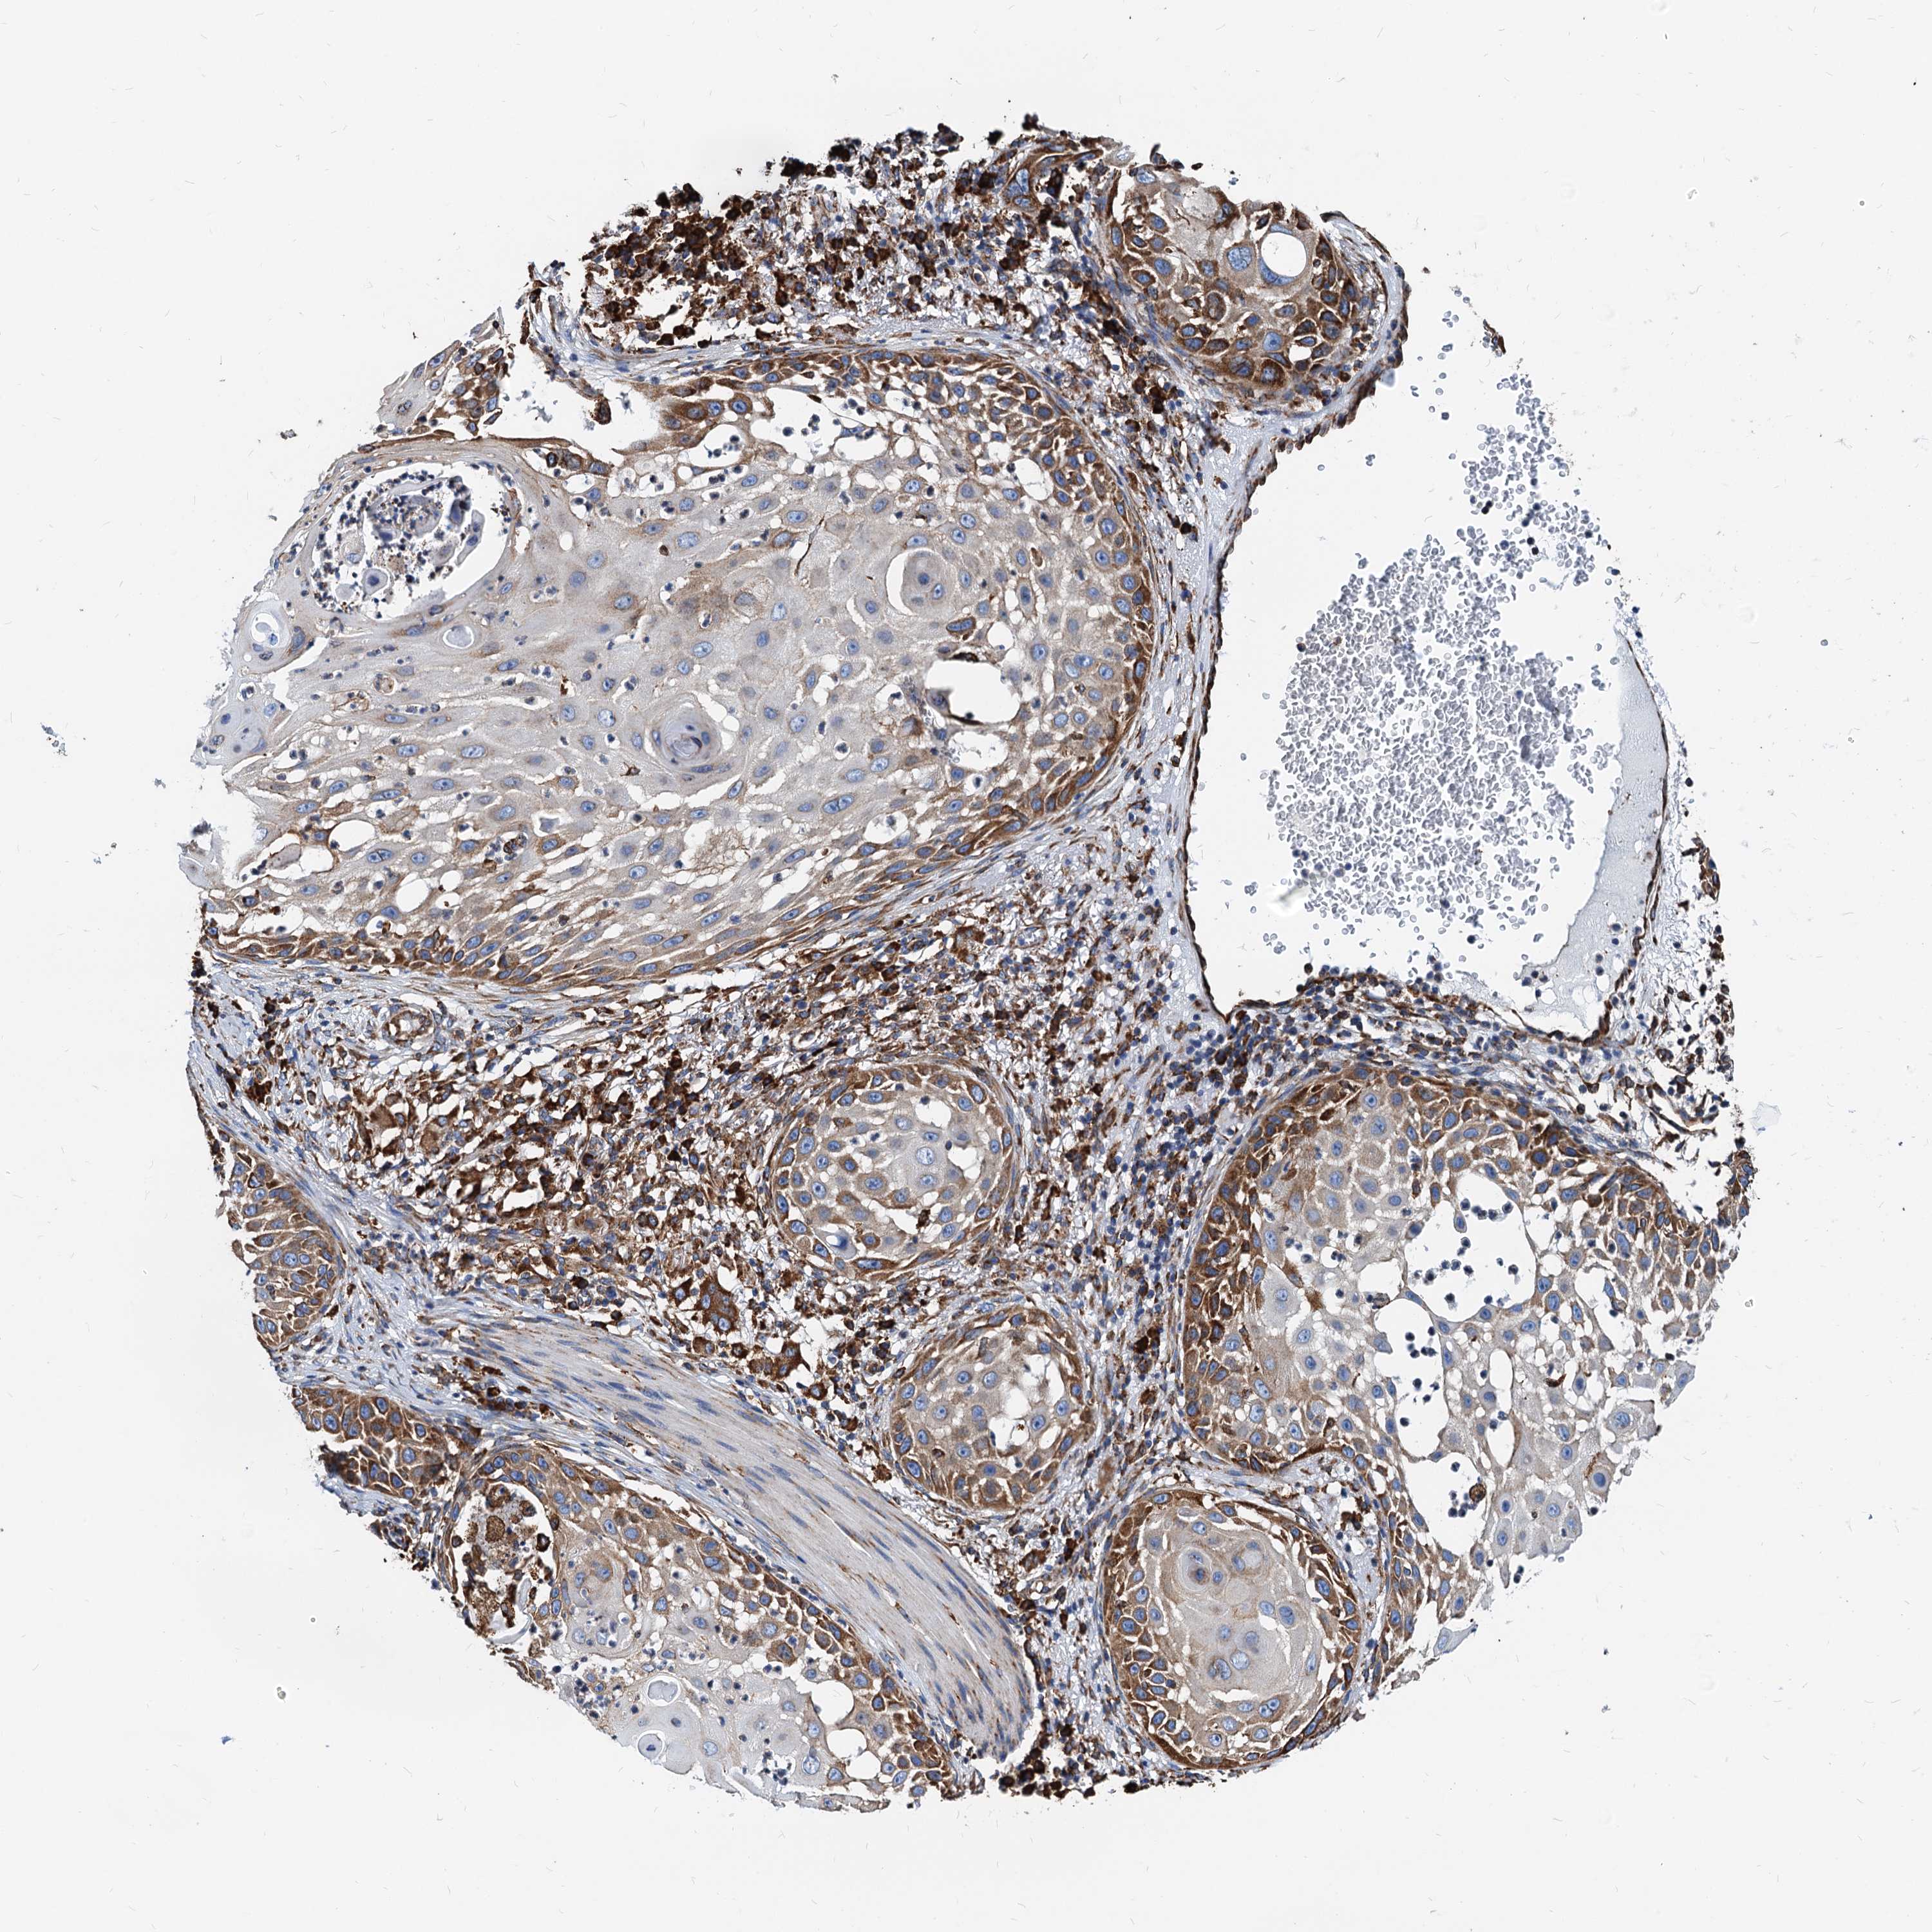

SKIN CANCER - Protein expressioni

A mouse-over function shows sample information and annotation data. Click on an image to view it in a full screen mode. Samples can be filtered based on level of antibody staining by selecting one or several of the following categories: high, medium, low and not detected. The assay and annotation is described here.

Each image is clickable and will lead to virtual microscopy that enables deeper exploration of all samples and also displays staining intensity scores, fraction scores and subcellular localization as well as patient and tissue information for each sample.

Antibody HPA038845

Antibody CAB005221

Staining

High

Strong

>75%

Location

Nuclear

Basal cell carcinoma